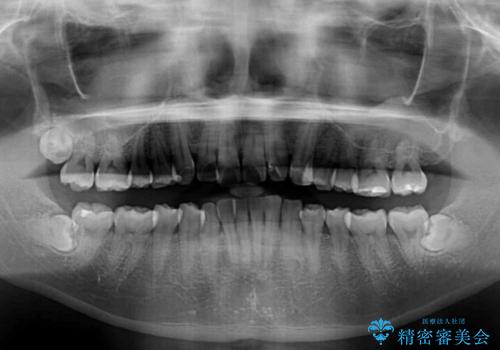

- 上下前歯のデコボコとクロスバイトを気にして来院された患者様です。

インビザラインを用い、IPR(歯と歯の間を削る)と歯列全体を拡大させることで、歯並びを整えていくこととしました。

毎日22時間の装着時間を徹底してくださったのですが、左右ともに臼歯が咬合しなくなるという、インビザライン独特の症状が強く長く続いてしまい、終了するまでに長期間を要してしまいました。